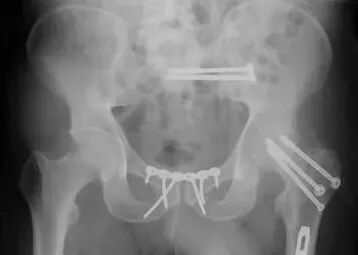

2)骨盆骨折

30min,三个决定:

• 开放性骨折,立即止血;

• 骨盆制动(10-15min);

• 观察10-15min,血流动力不稳定,能否手术?

图片

血流动力学稳定,在7天内手术?

3)髋臼骨折(伤后5-7天)